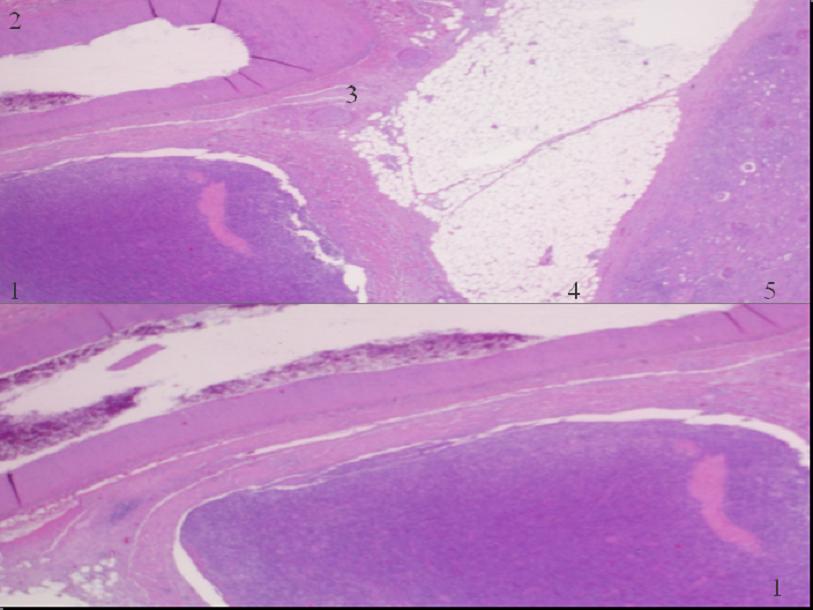

Los tumores neuroectodérmicos primitivos de origen renal (rPNET) son neoplasias excepcionales y pertenecen al grupo de tumores neuroectodérmicos periféricos malignos. Son tumores extremadamente agresivos, con tendencia a la recurrencia y a la metastatización temprana. Esta entidad pueden ser confundida con toda la variedad de tumores de células redondeadas de pequeño tamaño. De manera que es importante hacer el diagnóstico diferencial con ellas por sus implicaciones terapéuticas y pronósticas.Descargas